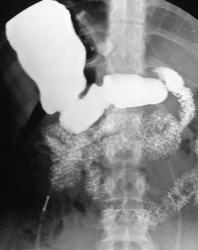

Не, тоже не то. верхние снимки выполнены в положении стоя, последние в положении лёжа. Подсказка есть в самих снимках. Я извиняюсь за качество; у меня флюроскопия записывается в виде цифрового видео, пришлось "ловить стоп-кадры для публикации.

Общая брыжейка-да, наиболее вероятно. Но не это главная причина, по которой я опубликовал данное наблюдение. Инверсии нет; я уже указал что снимки это стоп-кадры с записи флюорографического исследования, поэтому получается зеркальное изображение. В случае инверсии, я конечно бы разместил обзорный снимок. Патология исключительно в желудке, и это наглядно видно. Я понимаю что "играю-немного-не-по-честному", но я сразу указал что это именно загадка. "Подсказка"-это не дренаж; пациентка пришла амбулаторно.

Да, в настоящее время считается одним из самых эффективных методов. Показан пациентам с 3ей и 4ой степенью ожирения. Принцип простой; на проксимальный сегмент желудка накидывается манжетка; которая как петля захватывает желудок; как бы создавая искусственный стеноз на уровне петли и формируя из верхней части маленький резервуар. Этот резервуар быстро наполняется малым количеством пищи; и пациент чувствует насыщение. Люди за год теряют до 30-40 кг. При помощи зонда и имплантированного под кожу аппликатора с физиологическим раствором, можно контролировать степень сужения (диаметра петли). Одно из самых распространённых осложнений при таких процедурах - синдром "соскальзывания" петли. Slipped gastric band syndrome.

Не, тоже не то. верхние снимки выполнены в положении стоя, последние в положении лёжа. Подсказка есть в самих снимках.

Общая брыжейка-да, наиболее вероятно. Но не это главная причина, по которой я опубликовал данное наблюдение. Инверсии нет; я уже указал что снимки это стоп-кадры с записи флюорографического исследования, поэтому получается зеркальное изображение. В случае инверсии, я конечно бы разместил обзорный снимок.

Патология исключительно в желудке, и это наглядно видно. Я понимаю что "играю-немного-не-по-честному", но я сразу указал что это именно загадка. "Подсказка"-это не дренаж; пациентка пришла амбулаторно.

Предлагаю ознакомиться с этими картинками; они многое пояснят! Но, в моём наблюдении не просто ятрогения, но есть осложнение, постарайтесь логически догадаться какое.

Получается муфта соскользнула с желудка и уперлась в диафрагму, тем самым наверное поддавив абдоминальный сегмент пищевода